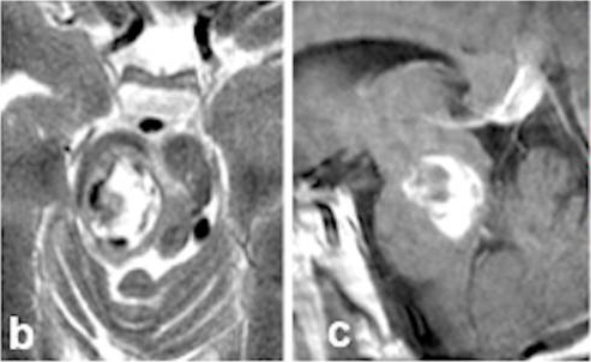

术前6个月

术前MRI清晰显示一个22mm的出血性病灶向尾侧延伸(图b-c)

巴教授经过周密评估,果断决定采用 “经右侧颞下入路” 实施手术。这个入路需要非常精细的操作,以安全抵达位于深部的脑干病灶。

术中发现,在滑车神经水平,被盖表面明显膨隆(箭头,图d),这正是出血病灶压迫的表现。在显微镜下,凭借精湛的技术和极大的耐心,巴教授及其手术团队成功地将致病的海绵状血管畸形病灶完整切除!术后复查影像和详实的手术记录都明确证实了病灶的全切。